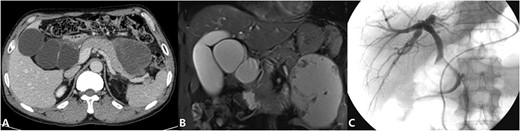

The patient is a 53-year-old man who was admitted to the hospital due to recurrent episodes of vague epigastric pain over a 4-month period. The patient had been diagnosed with Choledochal cysts and pancreatic pseudocyst in a local hospital before coming to seek treatment in our hepatological surgery department. Clinical evaluation revealed no yellowing of the skin or sclera, no abdominal wall varices, a soft abdomen without tenderness, and no abnormal masses felt. The liver and spleen were not palpable. The routine laboratory tests also were unremarkable. CT scan (Fig. 1A) showed cystic dilation lesion of the extrahepatic bile duct, which the largest one ~6.3 × 5.6 cm, and a mass of mixed density shadow in the pancreatic body and tail that measuring ~10.3 × 7.8 cm. MRI and MRCP (Fig. 1B) revealed multiple cystic dilation lesions in the common bile duct, which was considered as Choledochal cyst type I and a pseudocyst forming in the body and tail of the pancreas. ERCP (Fig. 1C) revealed that there is not dilation of the bile ducts and the cystic duct was partially developed, but the gallbladder was not developed. A multidisciplinary consultation was conducted by the hepatological surgery department in collaboration with the radiology department and endoscopy unit. The diagnosis is suspected to be a cystic lesion at the hepatoduodenal ligament, and it has been decided to perform preoperative ERCP followed by nasobiliary tube placement.